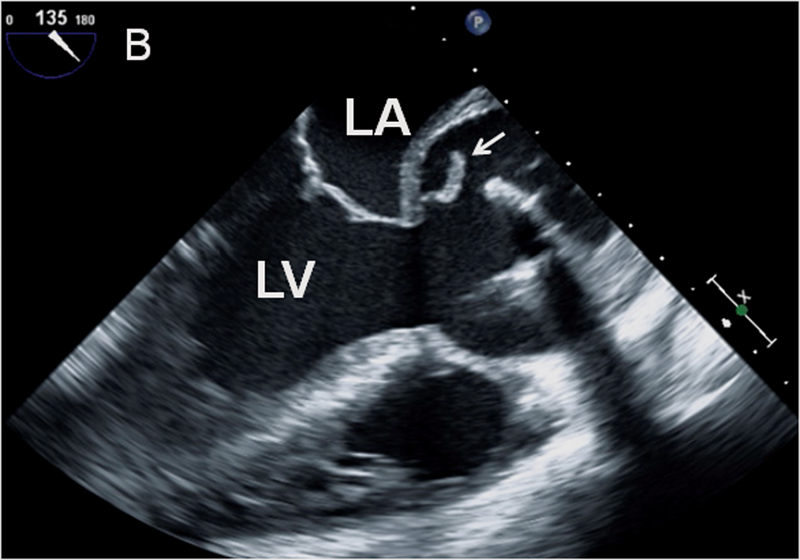

فحوصات تشخيصية لبعض امراض القلب والشرايين التاجية